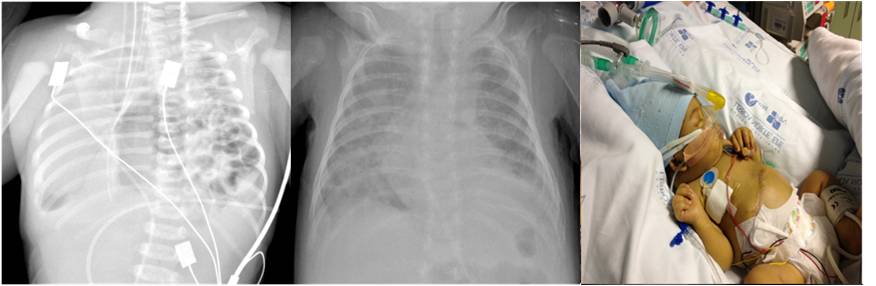

Atualmente a utilização de ECMO (oxigenação por membrana extracorporal) constitui a terapêutica de última linha no tratamento da insuficiência respiratória de doentes com hérnia diafragmática congénita. Apresentam-se os casos de dois recém-nascidos com hérnia diafragmática esquerda grave, com hipoxemia e hipertensão pulmonar refratárias às medidas máximas de terapêutica convencional, que necessitaram de suporte de ECMO para a normalização da oxigenação.